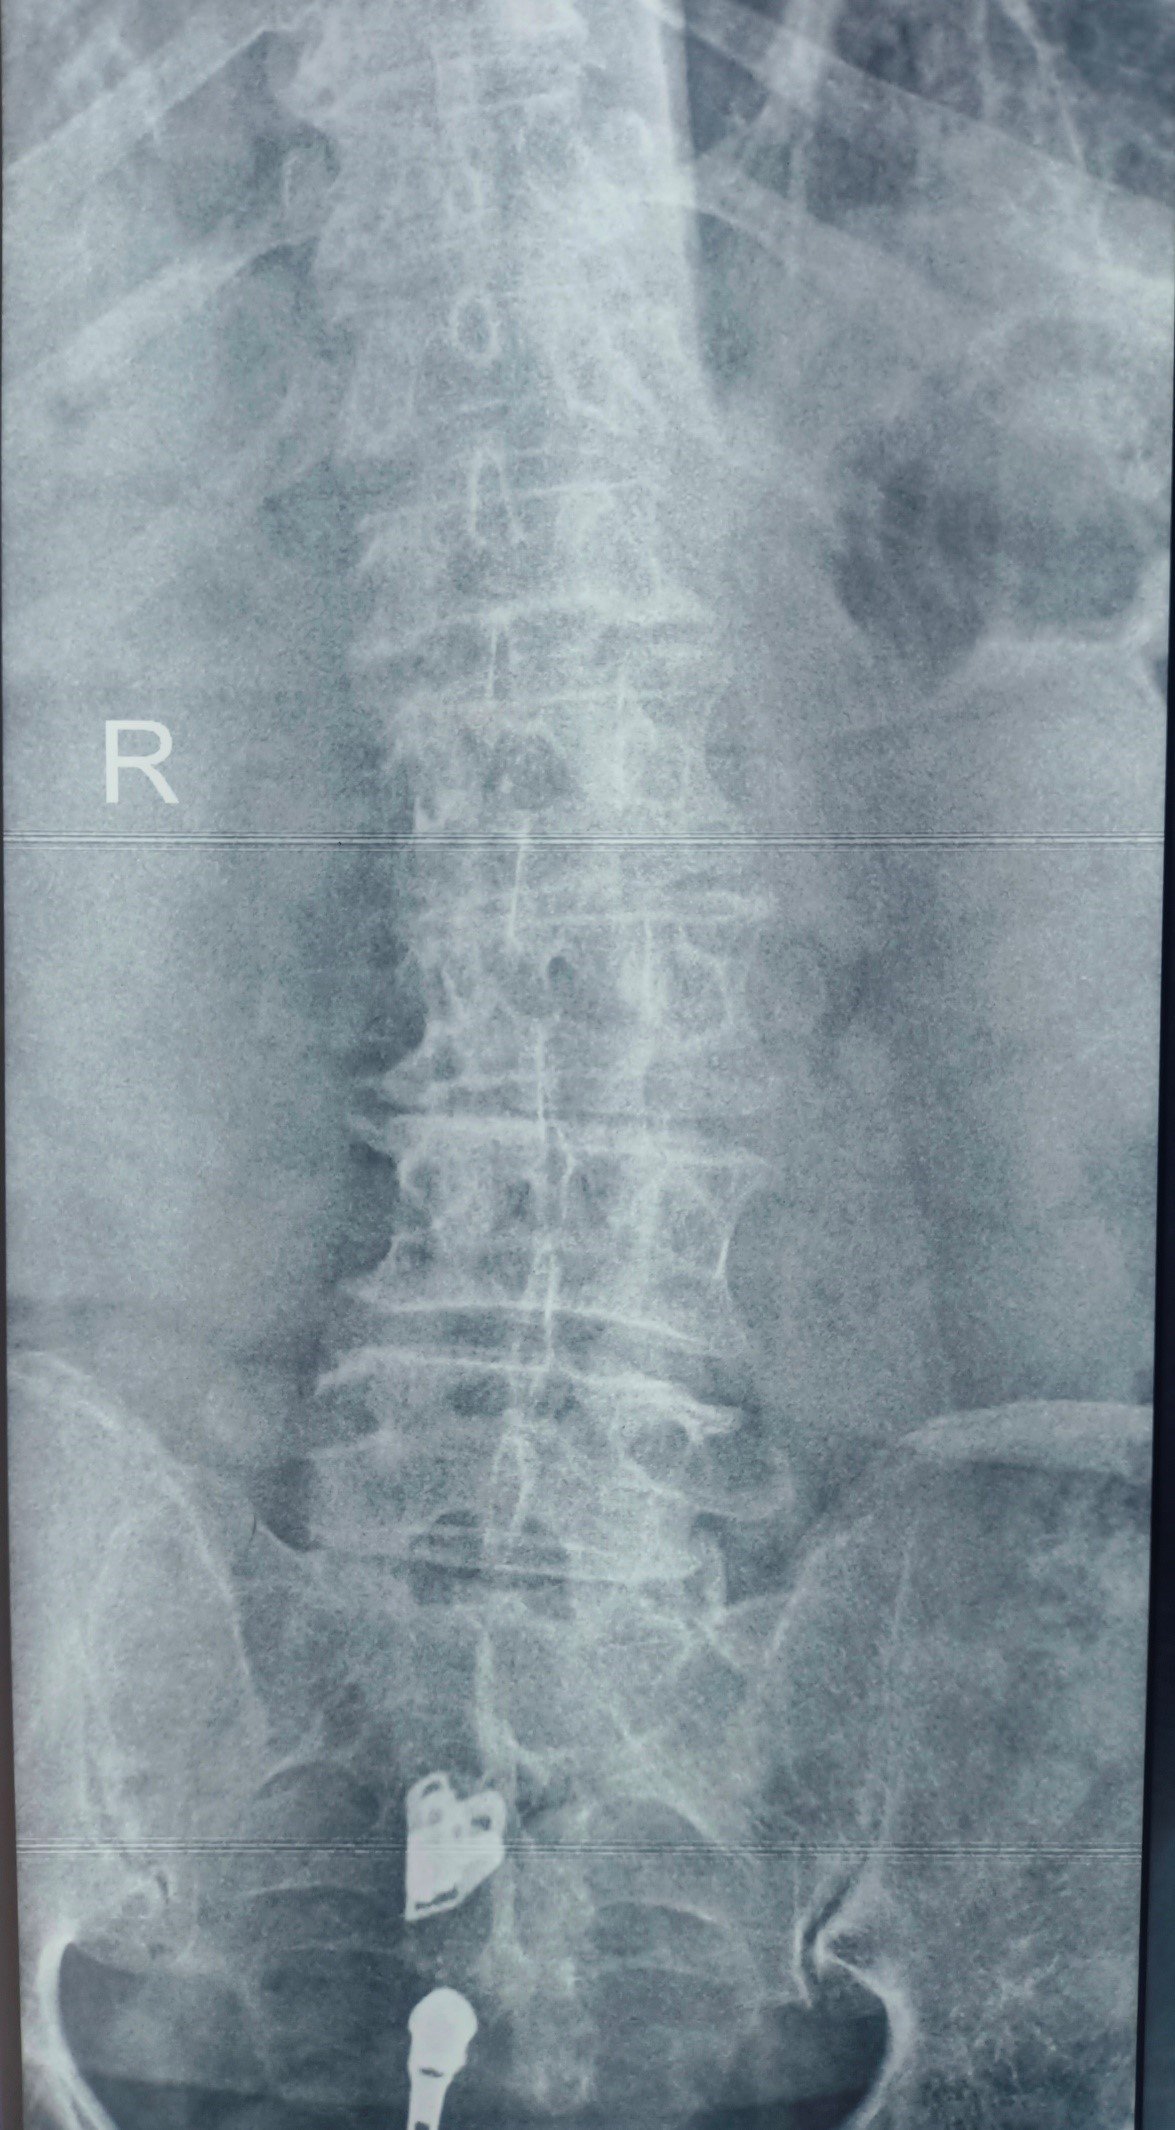

Cervical Disc Prolapse Treatment

Cervical Disc Prolapse Advanced Cervical Spine Care by Dr. Nitish Agrawal – Best Spine Surgeon in Pune Cervical Disc Prolapse, commonly known as slip disc in the neck, occurs when a disc in the cervical spine bulges or herniates and compresses nearby nerve roots or the spinal cord. This condition…